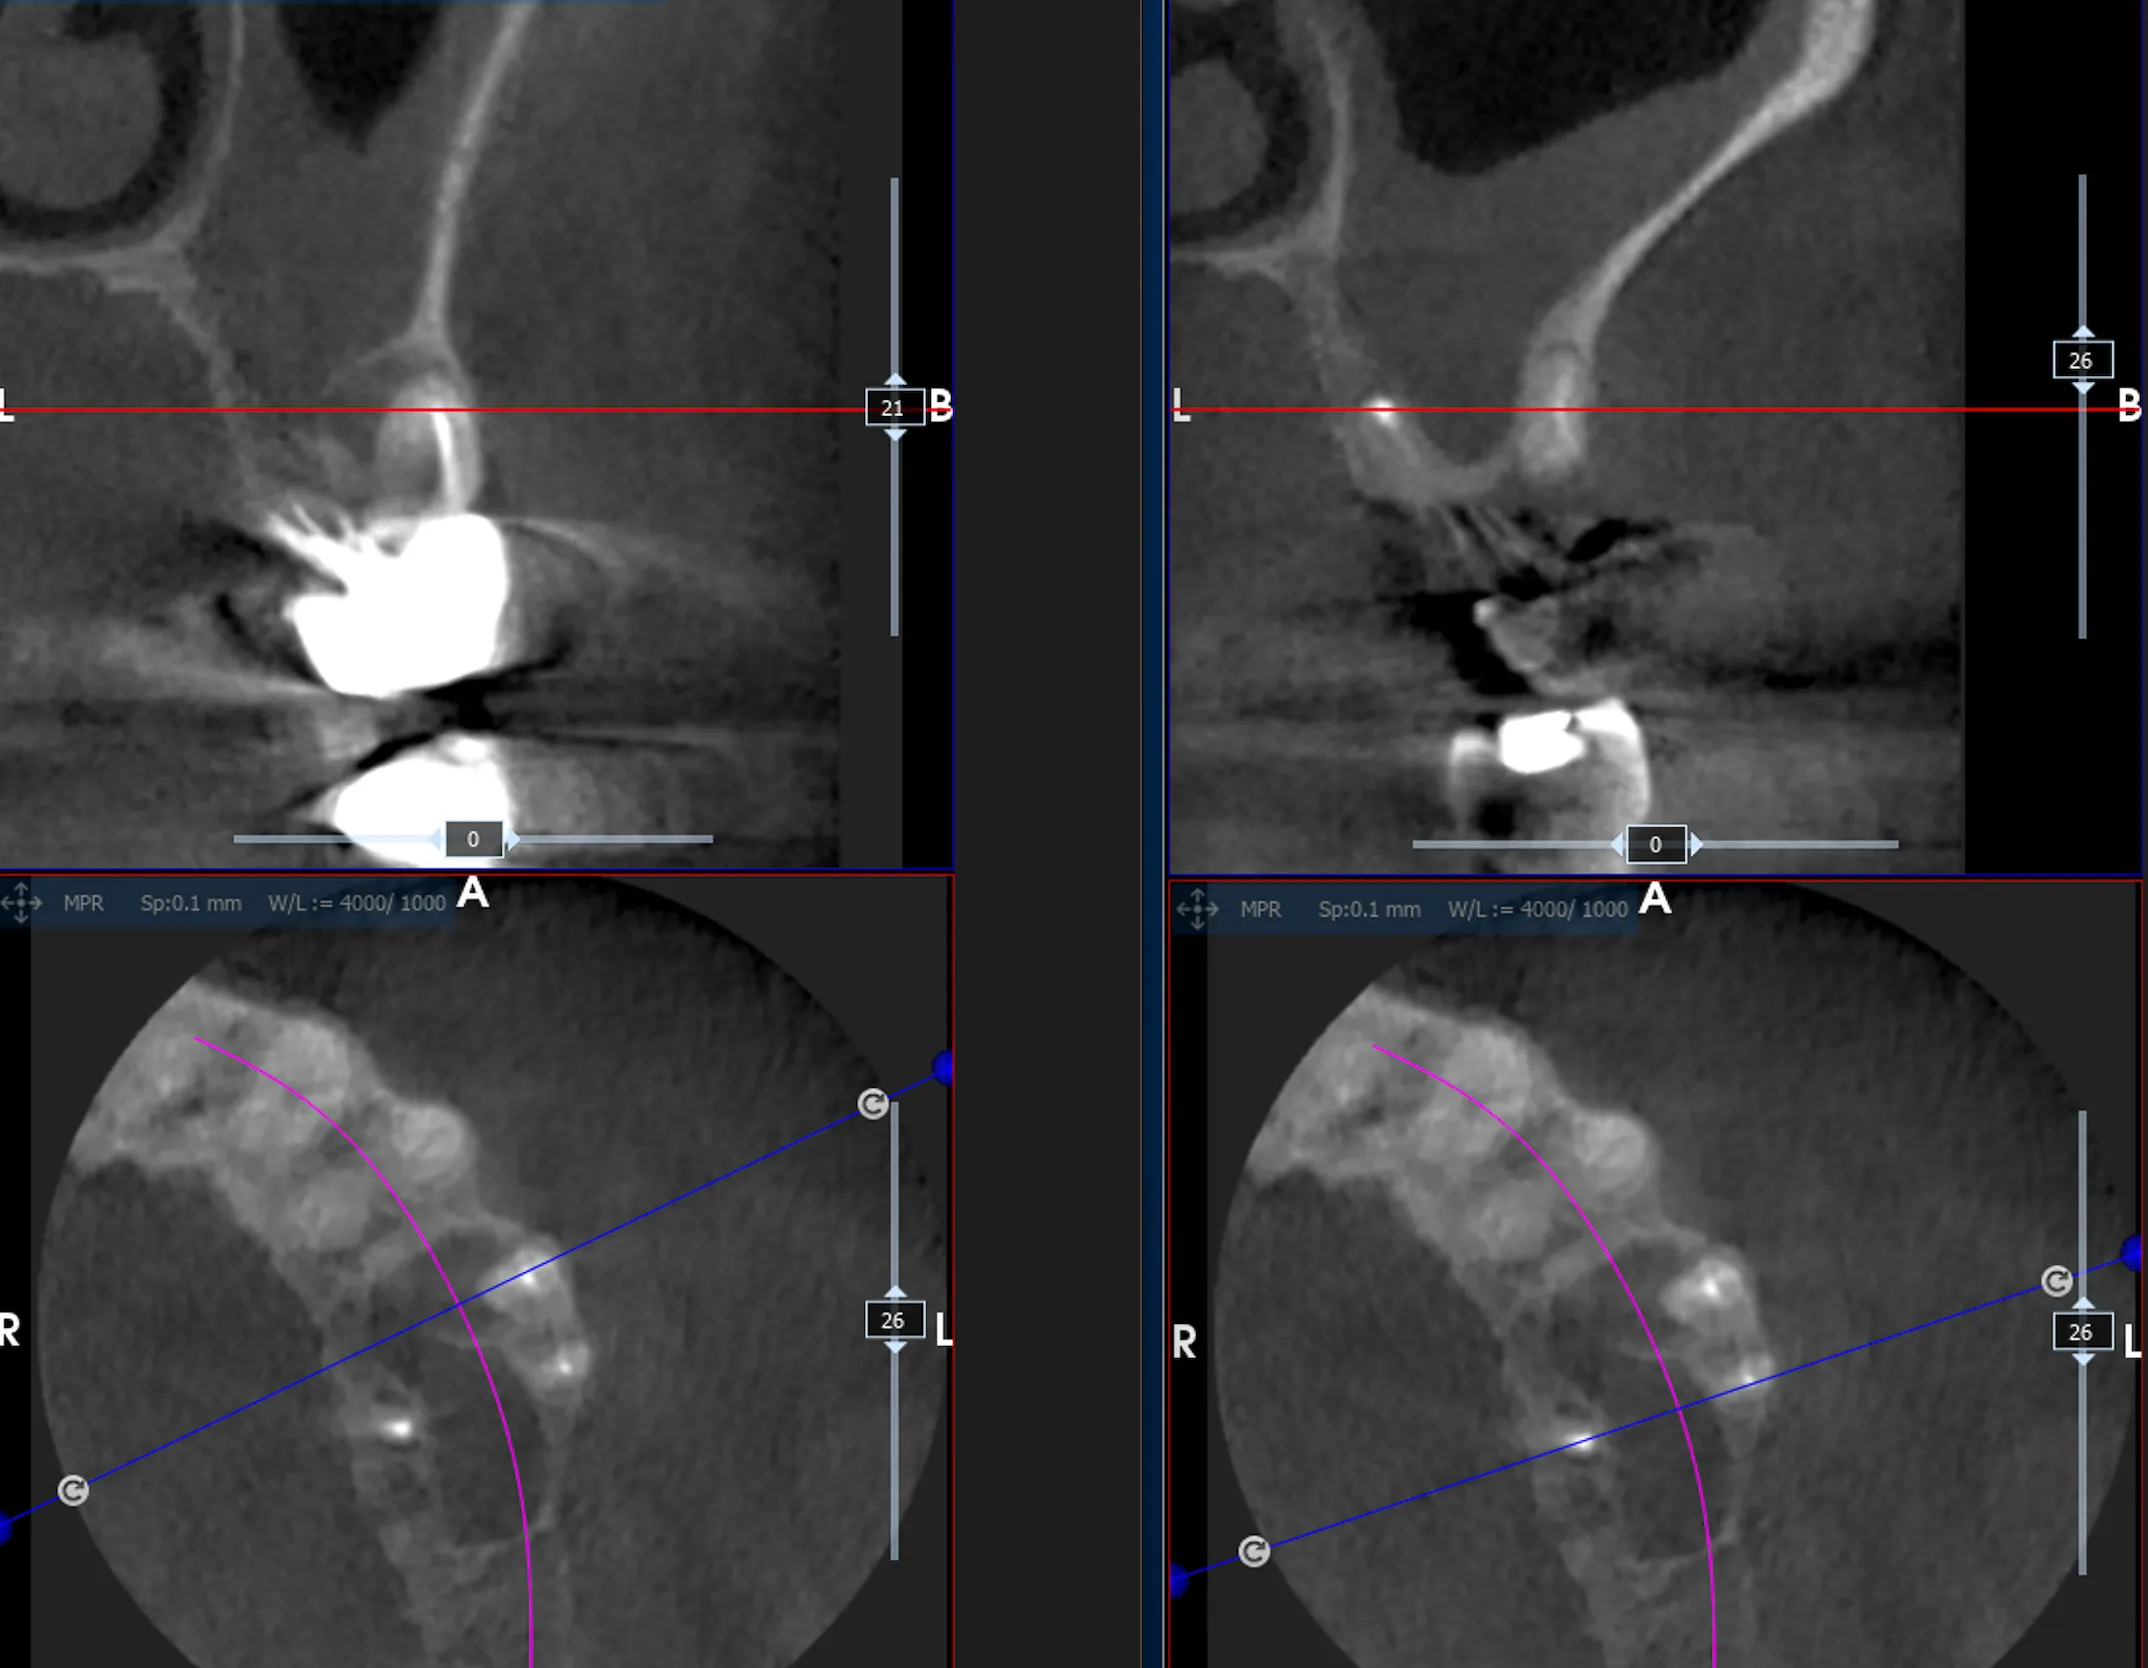

L’immagine che segue illustra l’aspetto preparatorio sulla CBCT.

Follow-up CBCT a 2 mesi

Il controllo tomografico a 2 mesi, nell’immagine che segue, ha mostrato:

- Sollevamento del seno con spazio sub-membranoso occupato da graft/osso neoformato in corrispondenza degli alveoli radicolari

- Riempimento degli alveoli stessi con integrazione del particolato

- Assenza di segni di comunicazione oro-antrale

Si apprezza una progressiva integrazione con l’osso nativo circostante.